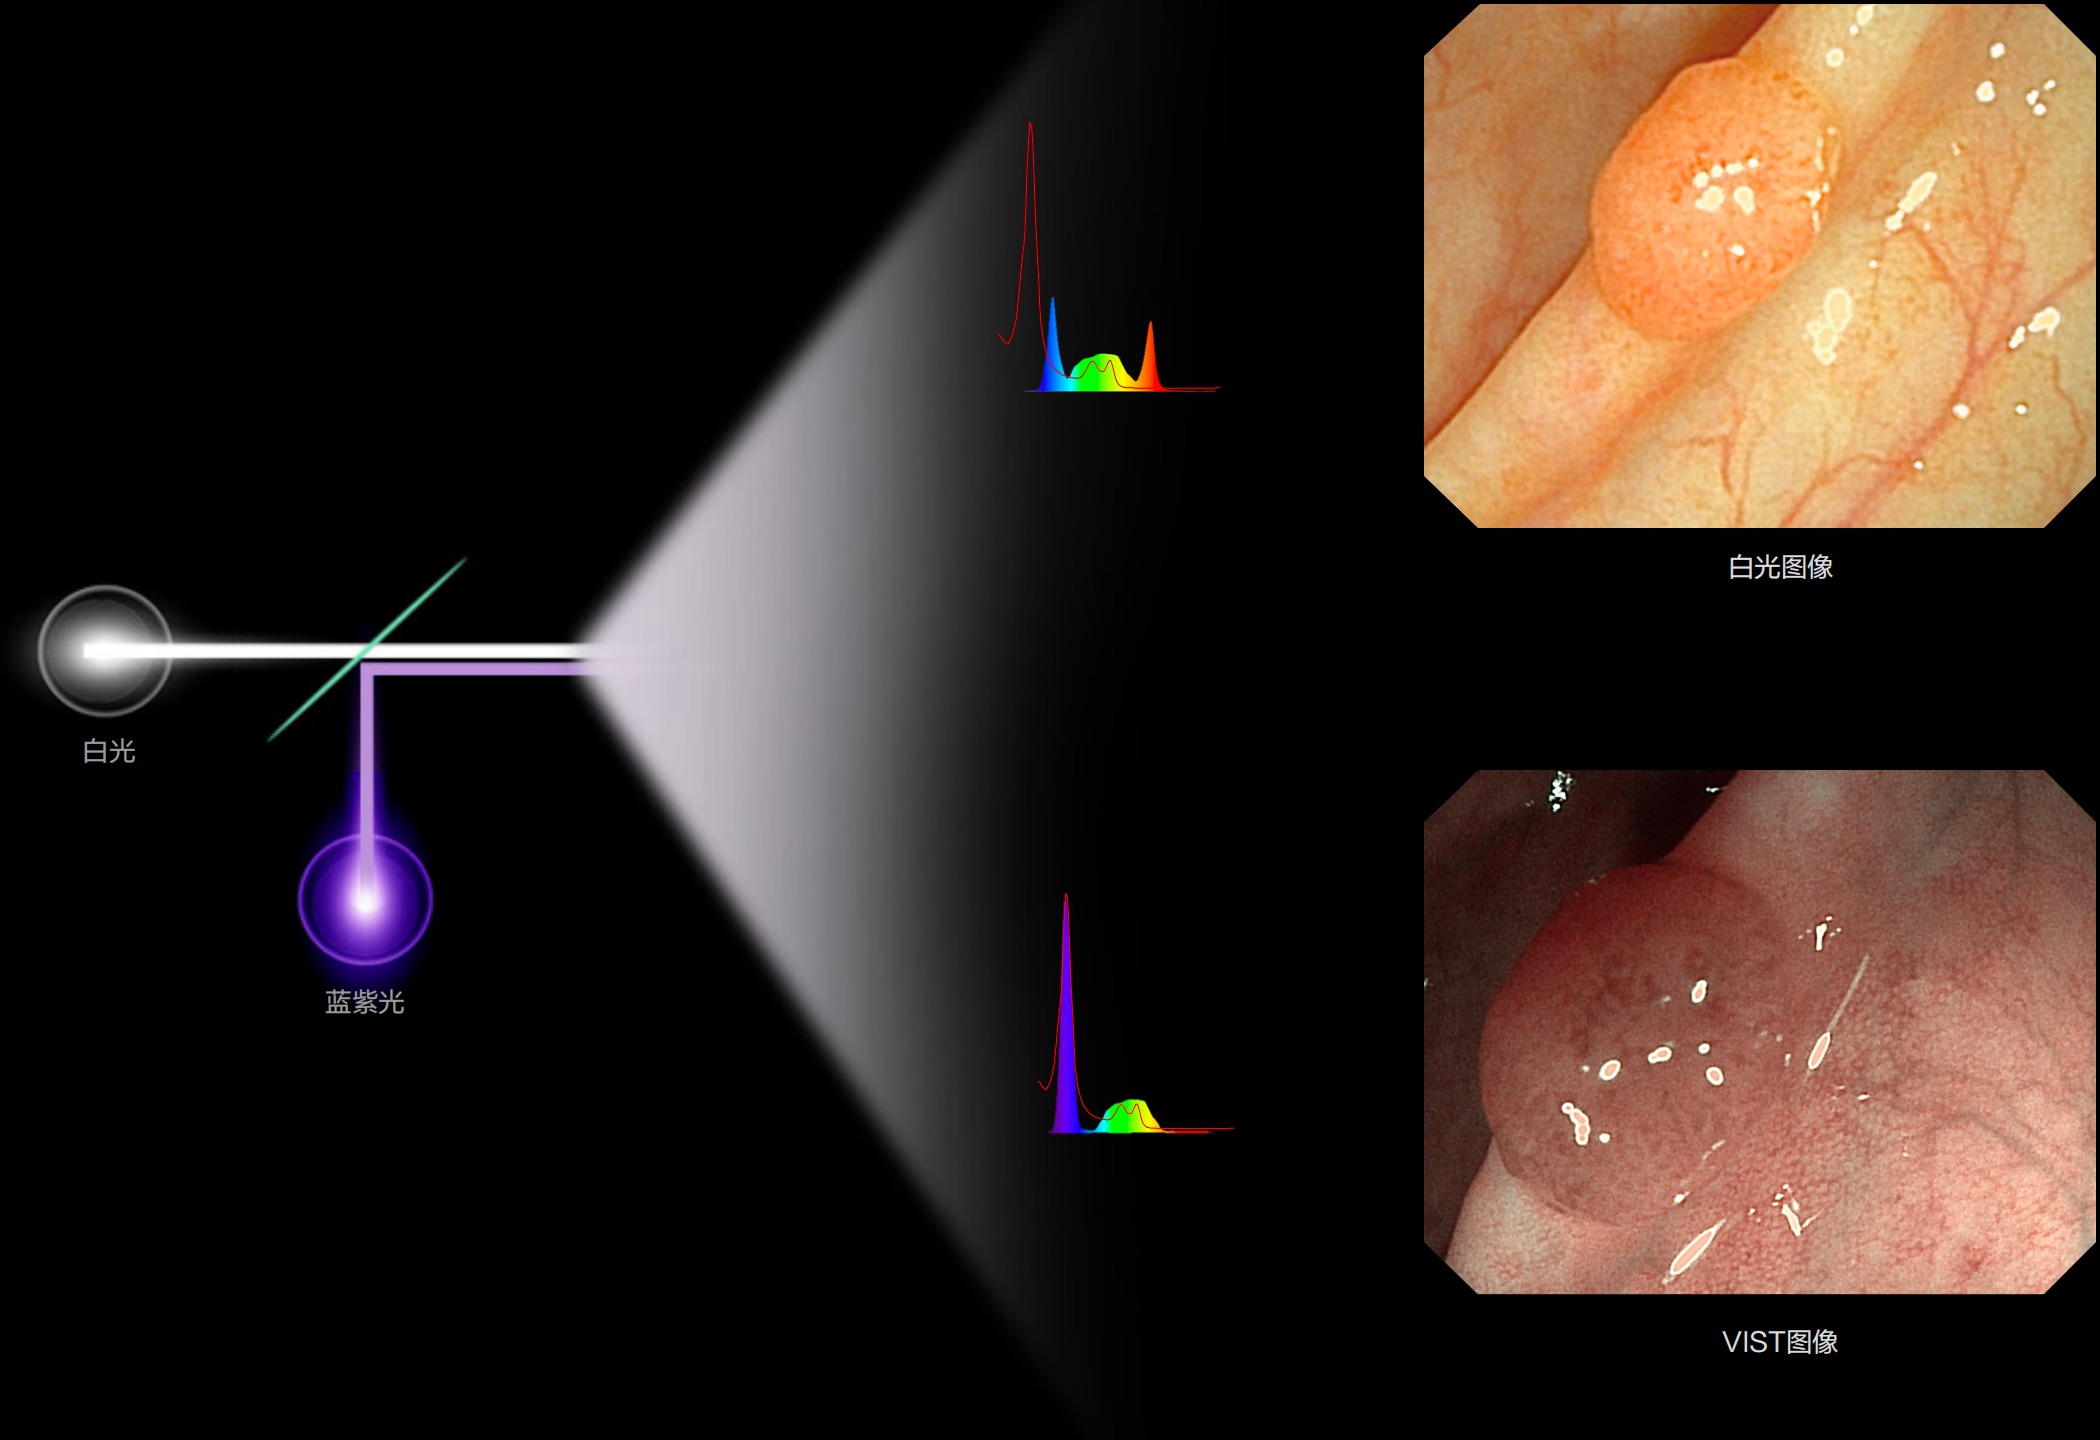

(Spectral Focused lmaging, SFI)

能够凸显黏膜浅层和中层血管轮廓,适用于中、远景观察下的病灶识别和早癌筛查。

白光图像

SFI图像

(Versatile Intelligent Staining Technology)

能够凸显黏膜浅层血管轮廓和黏膜表面微结构,适用于中、近景观察下的早癌精确诊断。